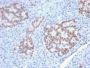

Applikationen IHC

IHC, FFPE (verified)

Positive Control

Jurkat cells. Small Intestine or Pancreas.

IHC (FFPE) (verified)